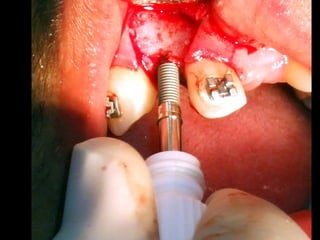

Primer tiempo quirúrgico; Exposición del maxilar para tomar una impresión del

hueso y poder elaborar la estructura implantaria.

Exposición del maxilar para tomar la impresión

Previamente se ha elaborado un portaimpresiones en acrílico de autopolimerización, el